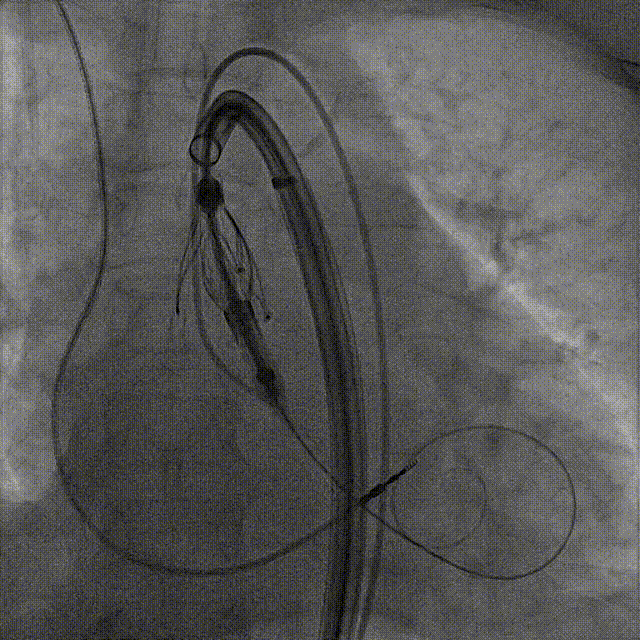

手术过程:5A 标准化流程SOP

术前右窦中心造影

大鞘植入

瓣膜对齐MARK

瓣膜调弯解离

瓣膜锚定键体位确认

瓣膜入窦

左窦确认

深度推进确认

起搏一键释放

术后造影